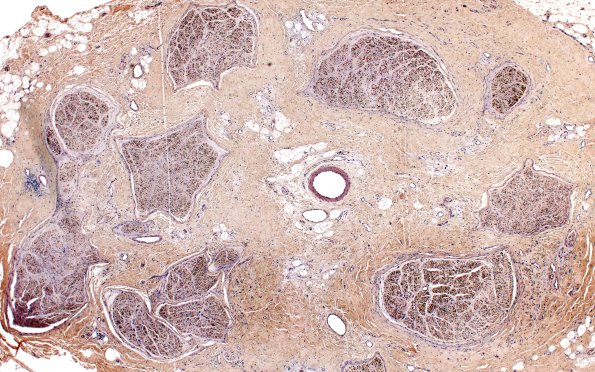

Washington University Experience | PERIPHERAL NEUROPATHY | 19 TRAUMATIC INJURIES | 6F1 Neuroma (Case 6) DISTAL NF 4X 1

There are numerous axons still in the fascicles but the size of the fascicles appear diminished due to axon loss. (NF IHC)